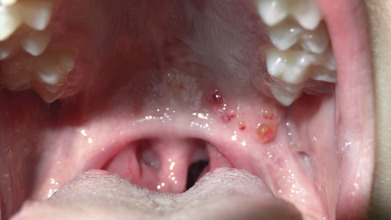

Vascular tumors range from red to blue, depending on the degree of vascular stasis and deoxygenation of hemoglobin. When associated with thrombosis or consumptive coagulopathy, the lesions often become hard and tender. The clinician should attempt to distinguish vascular proliferative lesions from vascular malformations, as the former tend to respond to beta blockers, whereas the latter do not. Malformations include nevus flammeus, salmon patch, nevus anemicus, and cutis marmorata telangiectatica congenita. Some vascular malformations are associated with overgrowth of surrounding tissues and can lead to considerable morbidity. This portion of the atlas will focus on the clinical findings of dermal tumors, including fibrous and vascular proliferations, as well as growths, in addition to those composed of muscles, nerves, and fatty tissue.